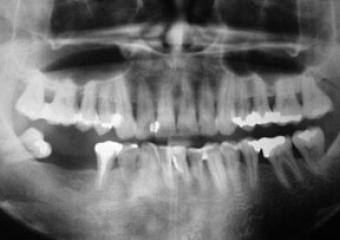

Raio X dos implantes instalados